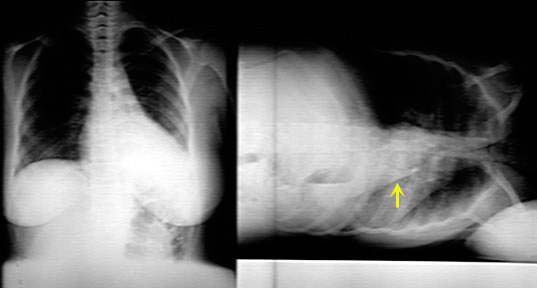

Resorptive Atelectasis of LUL

Cancer Lung

LUL atelectasis due to endobronchial obstruction. Once the bronchus is obstructed, there is no ventilation and the air gets absorbed. The distal lung is now devoid of air and becomes atelectatic.

Black arrowhead pointing to atelectatic LUL.

Signs of loss of lung volume:

Trachea (yellow arrow) is shifted to left.

White arrow is pointing to the bowing left oblique fissure. The fissure has moved forwards due to loss of LUL lung volume.